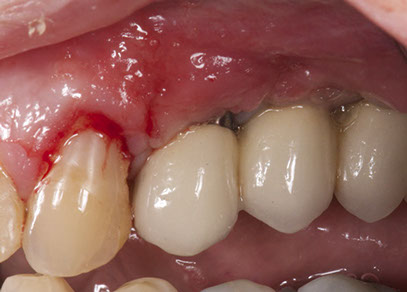

After 15 days of healing the patient came to the office and an improvement in the soft tissue level could be observed. Long term observation is needed to confirm the improvement of the soft tissue thickness and the partial coverage of the recession.

Although soft tissue management around peri-implant tissues is not always predictable, but as in teeth some approaches can be performed to solve soft tissue recessions around implants such as a coronally repositioned flap with simultaneous connective tissue graft.